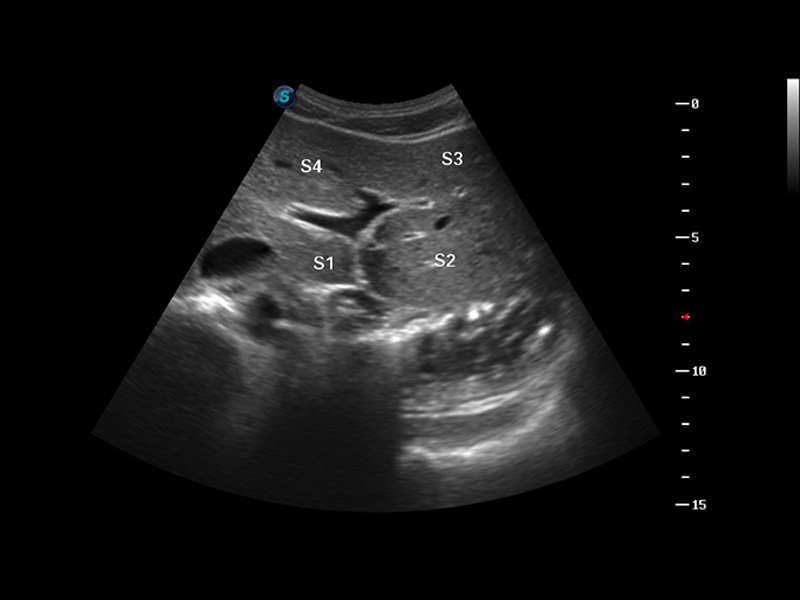

S8 EXP便携式彩色多普勒超声诊断仪是玖鼎集团研发的高端全身应用型便携彩超。高通道的VIS平台融合可视化(Visual)、智能化(Intelligent)和人性化(Smart)的特点,配以玖鼎集团自主研发生产的探头大家族,使您能够快速、准确的获得病人信息,提高工作效率的同时减轻疲劳。

μ-Scan微米成像

谐波成像

空间复合成像